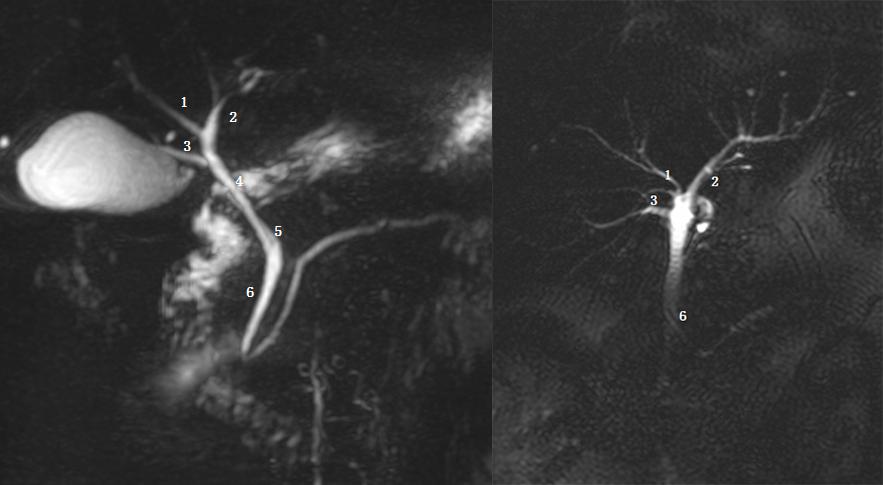

Ⅲc 型为为右后肝管汇入胆囊管。左图 1 为右前肝管,2 为肝左管,3 为右后肝管,4 为胆囊管,5 为胆总管;右图 1 为胆囊管,2 为右后肝管,箭头为胆囊结石。

Ⅳ型:右肝管汇入胆囊管。左图为胆总管远端梗阻患者,图示 1 为肝右管,2 为胆囊管,3 为肝左管,4 为胆总管。

由于副肝管位于胆囊三角或肝门附近,开口越低、越靠近胆囊管开口,手术时就越容易发生误伤。

Ⅴ型为副肝管的存在。图示 1 为肝右管,2 为肝左管,3 为副肝管,4 为肝总管,5 为胆囊管,6 为胆总管。